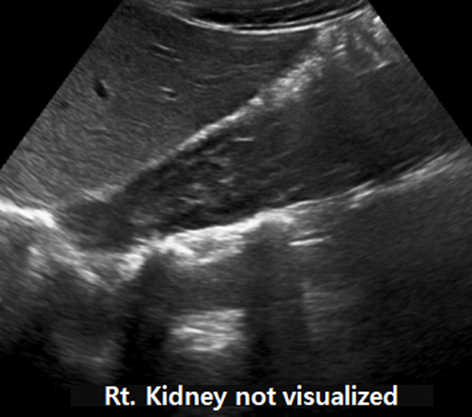

Ultrasound (US)

• May show:

• Absence of one kidney

• Cystic mass in the pelvis or retrovesical space

Findings:

There is congenital absence of the left kidney. Additionally, the left seminal vesicle is also absent.